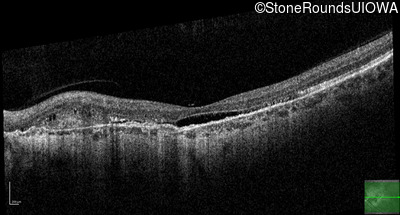

Pseudoxanthoma Elasticum (IID2)

Age at visit: 58 years